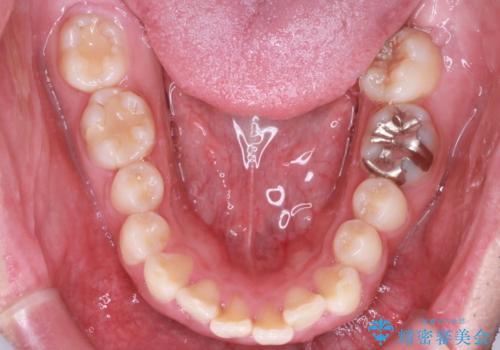

- 前歯の隙間と口元を主訴に来院されました。

インビザラインにて治療を行いきれいな歯並びをつくることができました。

奥歯の噛み合わせもきちんと仕上げることができました。